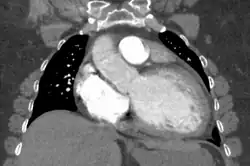

Dilated cardiomyopathy on CT

Generalized enlargement of the heart is seen upon normal chest X-ray. Pleural effusion may also be noticed, which is due to pulmonary venous hypertension.[28]

The electrocardiogram often shows sinus tachycardia or atrial fibrillation, ventricular arrhythmias, left atrial enlargement, and sometimes intraventricular conduction defects and low voltage. When left bundle-branch block (LBBB) is accompanied by right axis deviation (RAD), the rare combination is considered to be highly suggestive of dilated or congestive cardiomyopathy.[29][30] Echocardiogram shows left ventricular dilatation with normal or thinned walls and reduced ejection fraction. Cardiac catheterization and coronary angiography are often performed to exclude ischemic heart disease.[28]